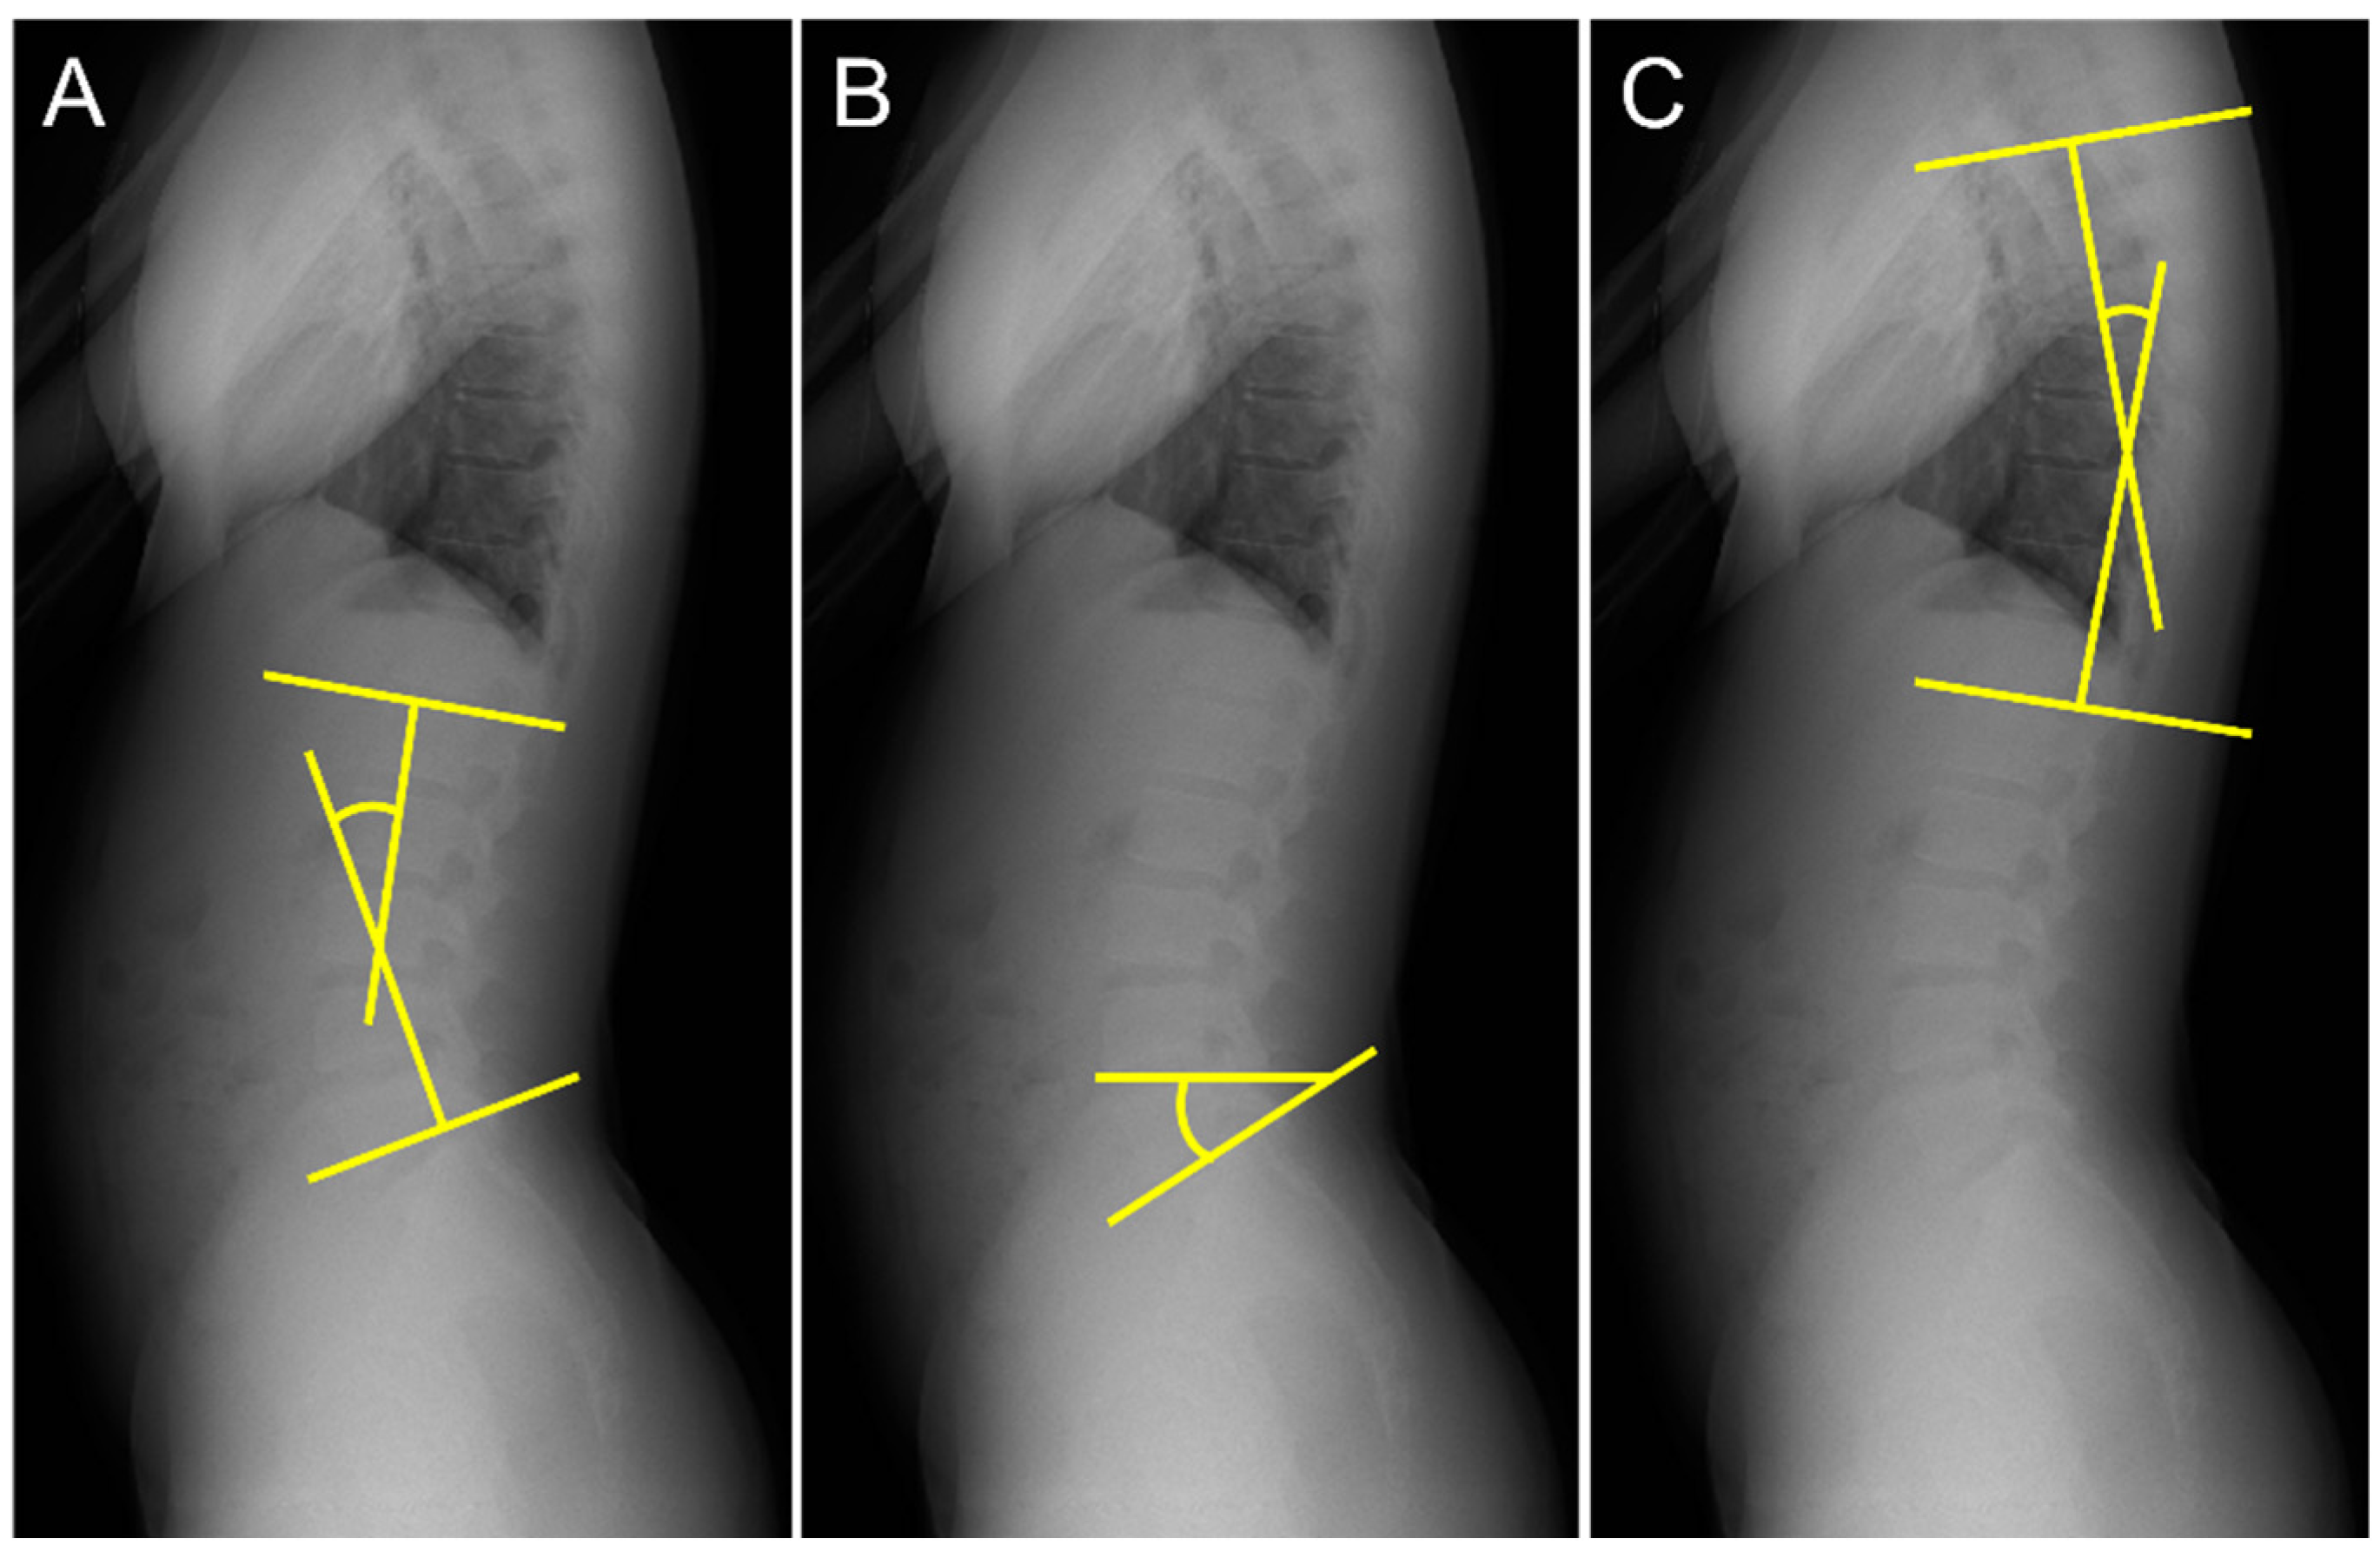

The lumbar lordosis angle (LL) was measured according to the method outlined in a previous study [18,19]. First, lines were drawn tangential to the superior endplate of L1 and inferior endplate of the L5. Second, perpendicular lines were drawn to each tangent. LL was defined as the acute angle formed by the intersection of the two perpendicular lines (Figure 2A). The sacral slope angle (SS) was measured using the procedure described in a previous study [20]. Lines were drawn tangentially to the superior endplate of S1 and horizontally. The SS was defined as the acute angle formed by these two lines (Figure 2B). The thoracic kyphosis angle (TK) was measured using the procedure described in a previous study [20]. First, lines were drawn tangential to the superior endplate of T5 and inferior endplate of T12. Second, lines perpendicular to each tangent were drawn. TK was defined as the acute angle formed by the intersection of the two perpendicular lines (Figure 2C).

Figure 2.

Measurement of spinal alignment. (A) Measurement of the lumbar lordosis angle (LL), (B) sacral slope angle (SS), and (C) thoracic kyphosis angle (TK).